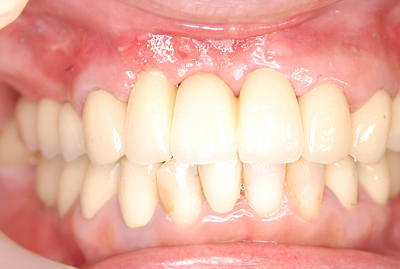

症例140代 男性 主訴 奥歯に歯を入れたい、しっかり噛みたい

治療前

治療後(5年経過)

主訴 奥歯がない為、食事が不自由である。入れ歯は煩わしいので、固定制のインプラントにして欲しいと訴え来院。口腔内全体で6本のインプラントを埋入。仮歯にて神経筋機構、顎関節のバランスを整え、リハビリを経て、約5ヶ月後にジルコニアを装着。

リスクとしては、外科的侵襲がある。デメリットは、保険外診療の為、経済的負担がある。

費用 316万(税込) (オペ・仮歯・最終補綴物まで含む)